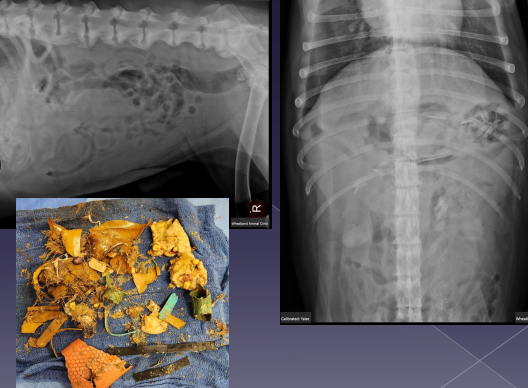

Gastric Foreign Body

Sig: history or suspicion of getting into things

Cs: vomiting, anorexia, dehydration, depression

Dt: contrast rads, US

Tx: Emesis (#1), Endoscopy (#2), Gastrotomy

Small Intestinal Foreign Body

Common to anchor: pylorus (dog)

under tongue (cat)

Causes erosion into mesenteric border

Cs: vomiting, depression, anorexia, diarrhea, pain, dehydration, palpable mass, string under tongue (C), weight loss

Dt: rads (stacking/bunching SI, pneumoperitoneum), US

Tx: gastroprotectants, Enterotomy (healthy bowel), R&A (damaged bowel), gastrotomy, (linear FB), fluids!!